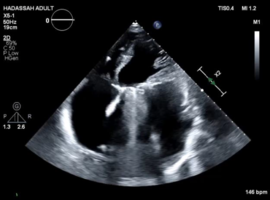

Mechanical Mitral Valve Failure after 40 Years: A Case Study in Timing and Decision-Making

Ouzan EJ*, Bloom A, Assley R, et al. (Israel)